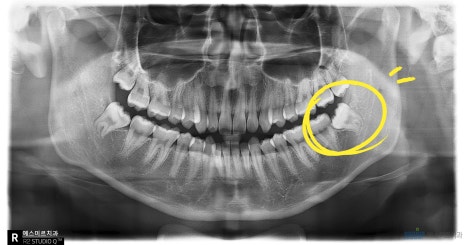

왼쪽 아래 음식물이 끼고, 양치관리가 안되어 잇몸이 붓고 통증이 생겨서 발치하는 경우